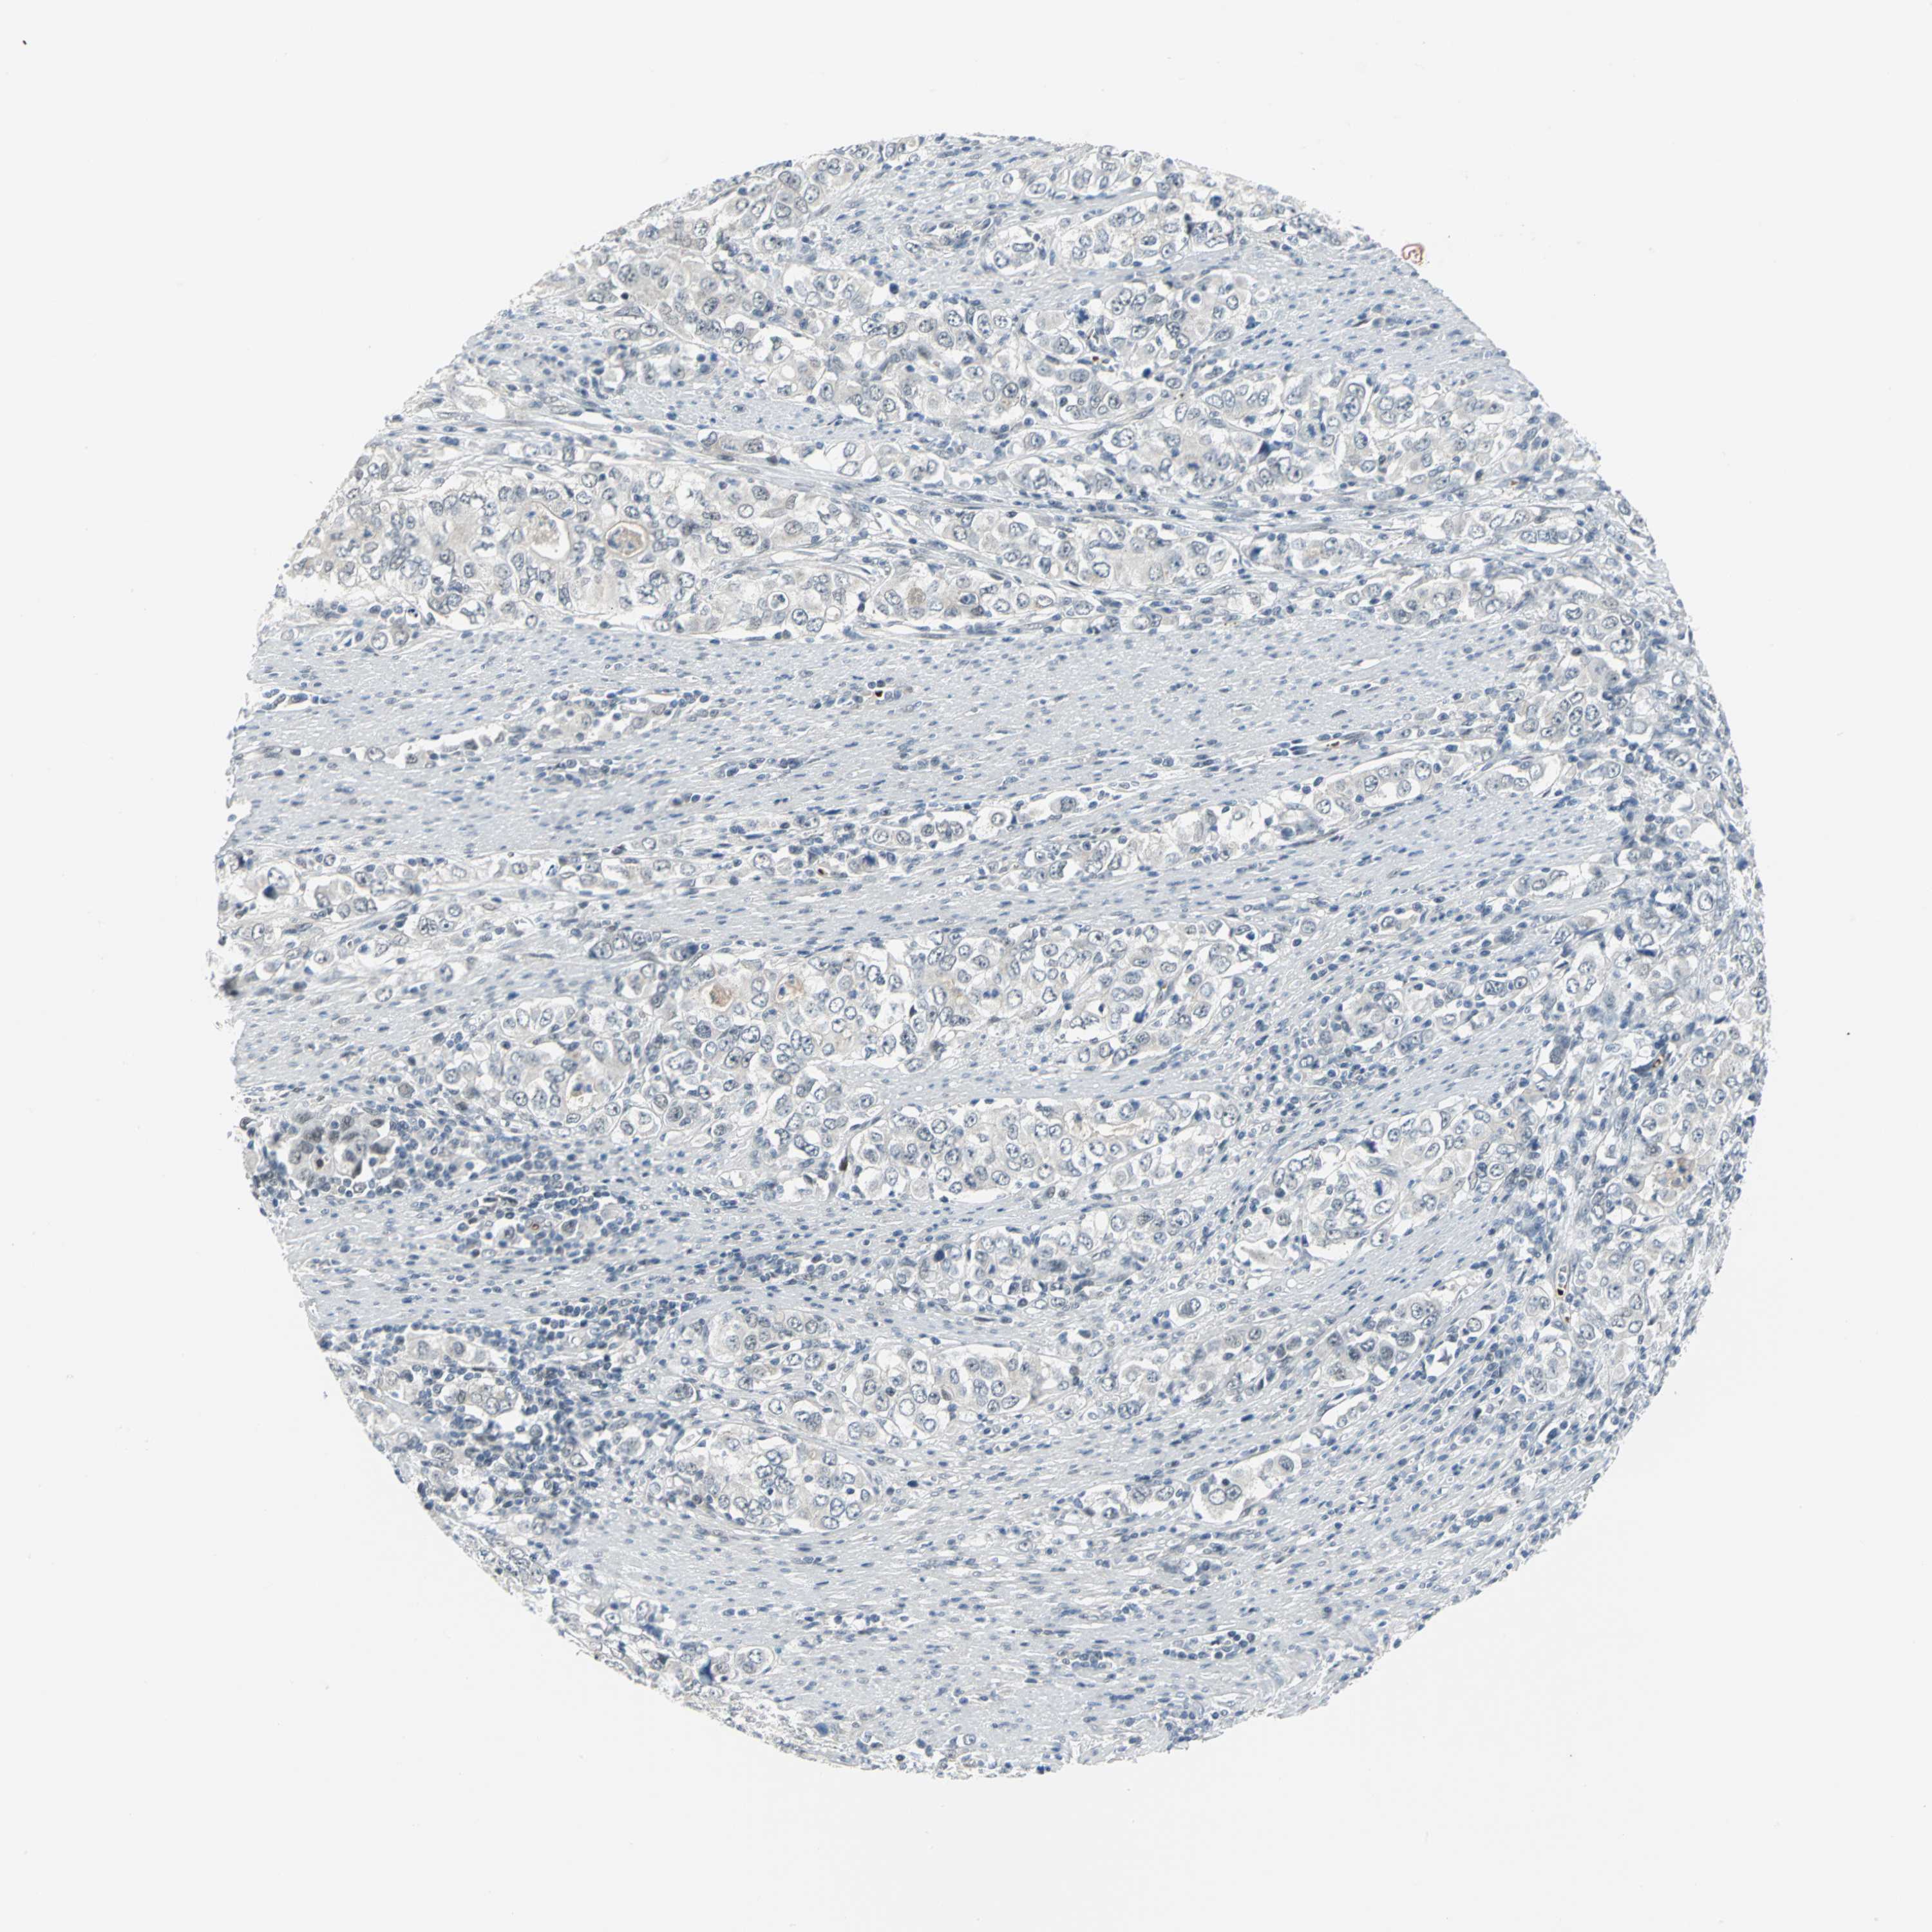

STOMACH CANCER - Protein expressioni

A mouse-over function shows sample information and annotation data. Click on an image to view it in a full screen mode. Samples can be filtered based on level of antibody staining by selecting one or several of the following categories: high, medium, low and not detected. The assay and annotation is described here.

Note that samples used for immunohistochemistry by the Human Protein Atlas do not correspond to samples in the TCGA dataset.

Antibody stainingi

Antibody staining in the annotated cell types in the current human tissue is reported as not detected, low, medium, or high, based on conventional immunohistochemistry profiling in selected tissues. This score is based on the combination of the staining intensity and fraction of stained cells.

Each image is clickable and will lead to virtual microscopy that enables deeper exploration of all samples and also displays staining intensity scores, fraction scores and subcellular localization as well as patient and tissue information for each sample.

Antibody HPA005534

Staining

High

Medium

Low

Not detected

Intensity

Strong

Moderate

Weak

Negative

Quantity

>75%

75%-25%

<25%

None

Location

Nuclear

Cytoplasmic/membranous

Cytoplasmic/membranous,nuclear

Adenocarcinoma, NOS

Adenocarcinoma, High grade